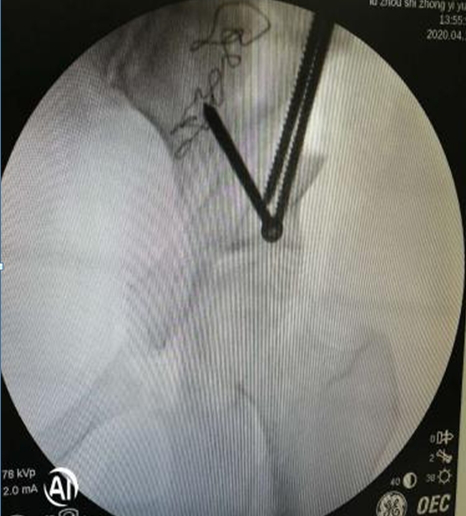

術(shù)中,左側(cè)髖臼周圍截骨

在李彬主任的帶領(lǐng)下,肖女士進行了髖臼周圍截骨術(shù)PAO保髖治療:調(diào)整髖臼位置,使髖關(guān)節(jié)的旋轉(zhuǎn)中心適度內(nèi)移;增加髖臼對股骨頭的覆蓋,增加負重的關(guān)節(jié)面,降低了髖關(guān)節(jié)負重面軟骨的應(yīng)力,達到了延遲或阻斷髖關(guān)節(jié)炎進展的目的,延長了自身髖關(guān)節(jié)的使用壽命。目前,患者恢復(fù)良好。